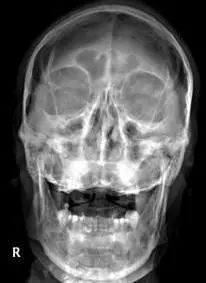

患者,男性,75岁,因外伤致颈部疼痛伴活动受限7天入院。患者入院前在当地医院确诊为:枢椎齿状突骨折Anderson-D’Alonzo分型Ⅱ型。

经过全程监护和系统治疗,患者术后恢复良好,骨折解剖复位,复查X线及CT显示固定位置佳,术后3天下地行走,术后4天即出院回家休养。

枢椎齿状突骨折前路空心螺钉固定术